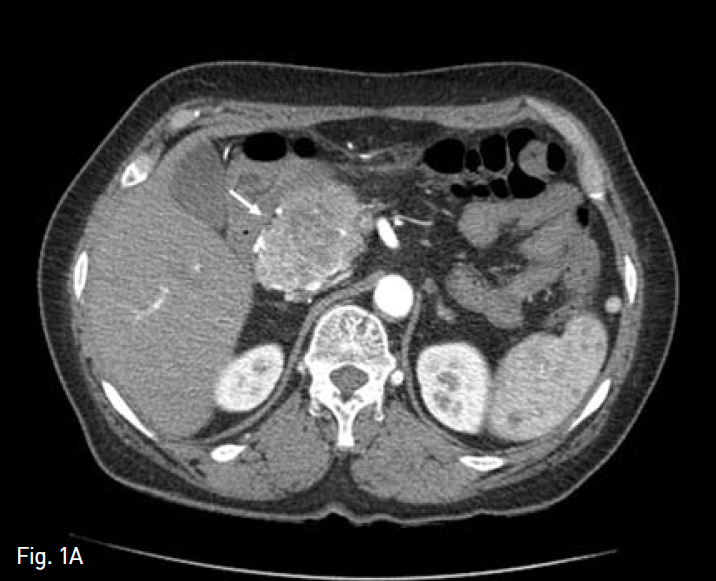

췌장 두부에 낭선종(Cystadenoma)으로 유문 보존 췌십이지장 절제술(PPPD)를 시행받은 환자로(Fig. 1A,B), 수술 2개월 후 지속적인 발열이 있어 내원하여 시행한 복부 전산화 단층 촬영상 간 우엽의 다발성 간농양과 함께 우엽 담관의 확장 소견이 보였고(Fig. 2), 경피경간 담도 배액술(PTBD)(Fig. 3A) 및 농양 배액술(Fig. 3B)을 시행받고, abscess content를 배양하여

Fig. 1

Contrast-enhanced axial abdominal CT image A shows a bulky, low attenuated mass lesion with hypervascularity in pancreatic head portion (white arrow). So, our surgeon performed pylorus-preserving pancreaticoduod enectomy with Traveso method (schema in B).